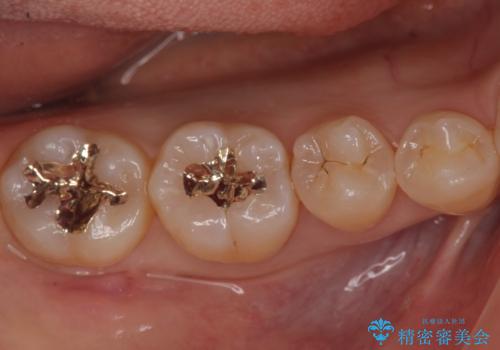

- 銀歯をやりかえたいが他院で抜歯と言われセカンドオピニオンで来院。適合の悪い被せ物が入っており、まずは古い材料、虫歯をとり保存可能か確かめる必要があり、拡大鏡下で全て取り除いたら歯質が歯茎の中まで虫歯がありました。このまま無理やり型取りをして被せ物を作っても不適合な被せ物が入る可能性が高いため歯茎を切り取る手術(ディスタルウェッジ)を行いました。そして再根管治療を行いゴールドの被せ物で治療を行いました。

適合の良い被せ物が入り大変満足して頂けました。